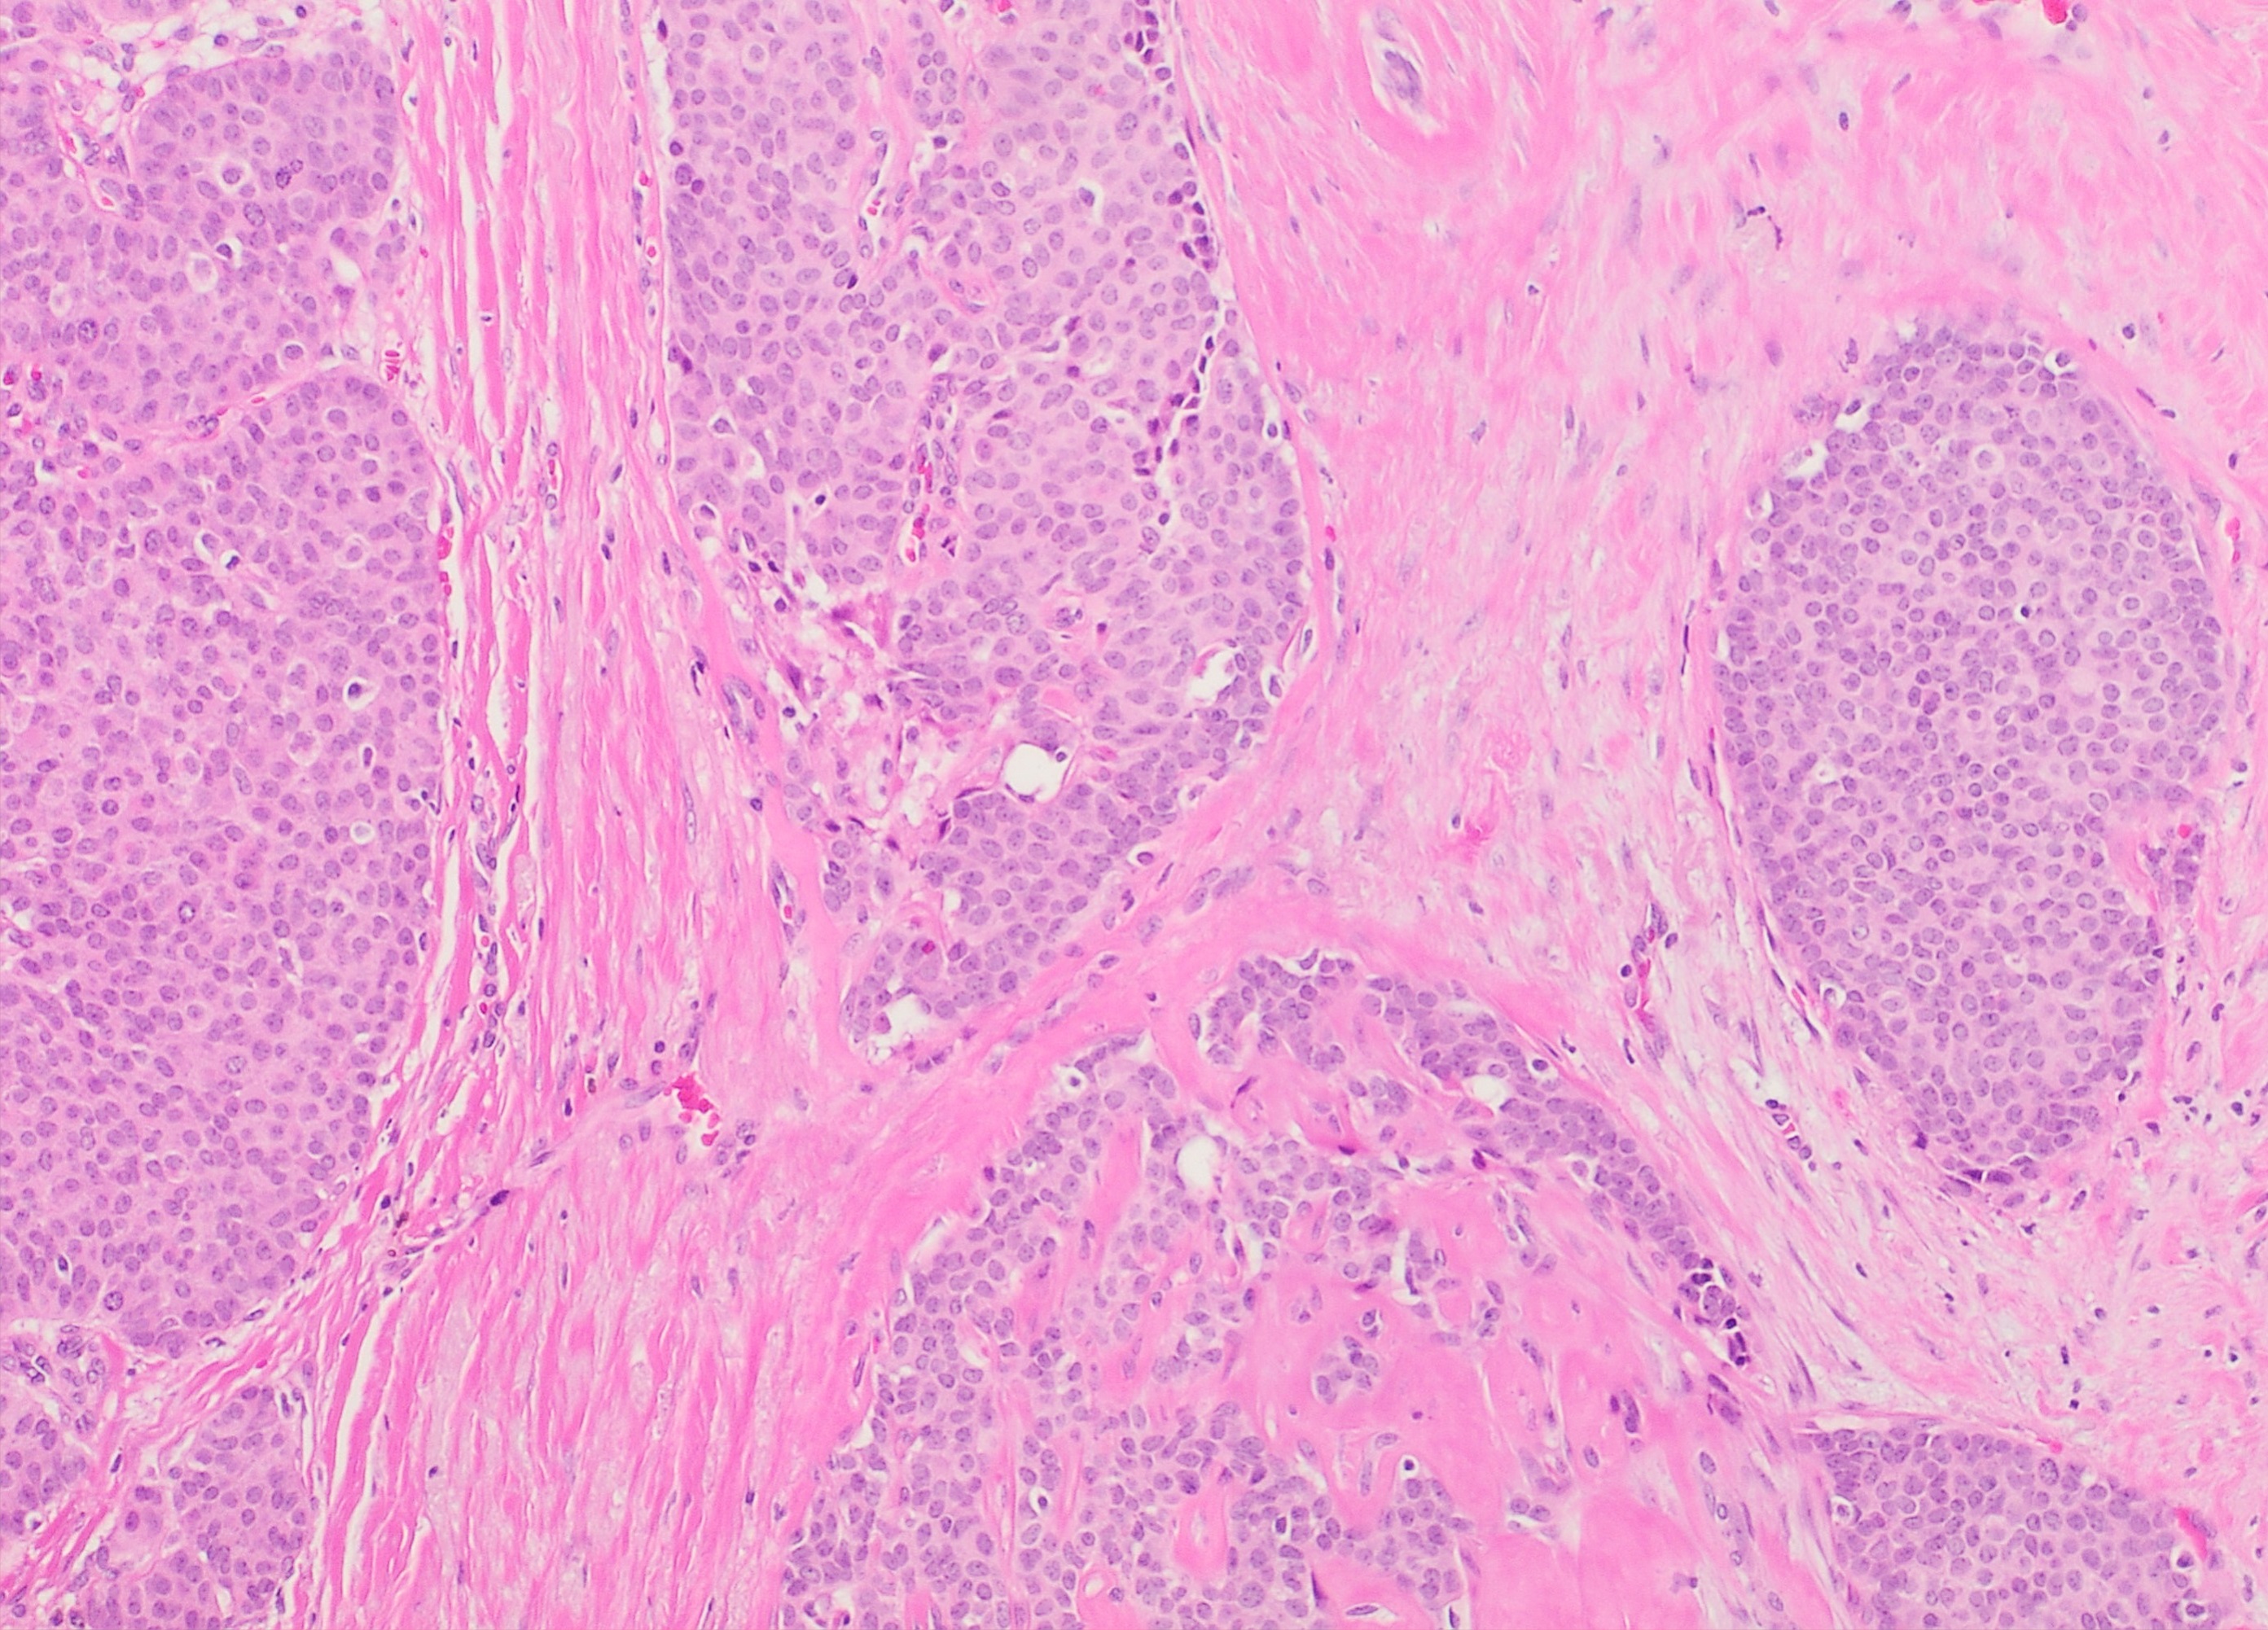

초기에 발표된 침윤성 유두상 암종(IPC) 사례 중 다수는 침윤성 캡슐화 유두상 암종(EPC) 또는 고형 유두상 암종(SPC)의 변형으로 여겨져, IPC에 대한 일관된 병리학적 데이터를 얻기 어려웠다.[7] IPC의 현미경적 조직병리학 연구에서는 다음과 같은 특징들이 보고되었다(오른쪽 고배율 현미경 사진 참조):

- '''1)''' 섬유 혈관 중심(core)을 둘러싸는 신생물성 상피 세포로 이루어진 뭉툭한 유두 모양 또는 관 모양 구조[1]

- '''2)''' 확장된 관 안에 위치하며, 다양한 크기의 미세 낭종과 괴사 (즉, 죽은 세포) 부위를 동반하는 유두[4]

- '''3)''' 신생물성 상피 세포로 덮인 섬유 혈관 중심이 종양의 대부분을 차지하는 경우[3]

- '''4)''' 종양의 90% 이상이 유두 모양을 보이며 주변 유방 조직 및/또는 유방 아래 가슴 근육으로 침윤하는 양상[22]

연구자들은 IPC 종양이 정의상 인접한 유방 조직이나 근육 조직으로 침윤하는 부위를 최소 한 곳 이상 가지며, 이 침윤 부위에는 근상피 세포가 없고, 일반적으로 주변을 둘러싸는 섬유성 막(캡슐)이 없다는 점에 동의한다. 이러한 특징들은 IPC 진단에 매우 중요하다.[6][7][20][22] 드물게, 관상 피내 암종 병변이 IPC 근처에서 발견되기도 한다.[3]